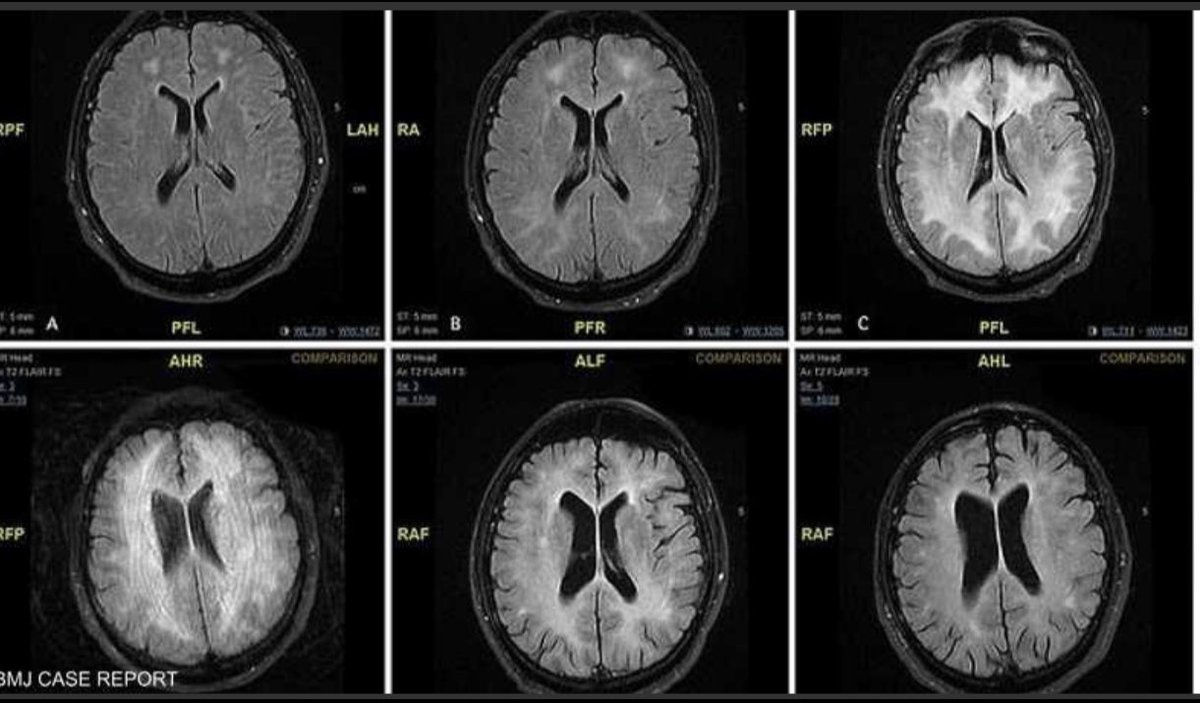

هنا حالة لمريض متعاطي للكوكايين تم تشخصيه بحالة "تلف المادة البيضاء المرتبط بالكوكايين" صورة من MRI🧠، يكشف تغيرات في أجزاء المادة البيضاء التي يبدو أنها "تآكلت". المادة البيضاء تلعب دور مهم في قدرات الادراكية.